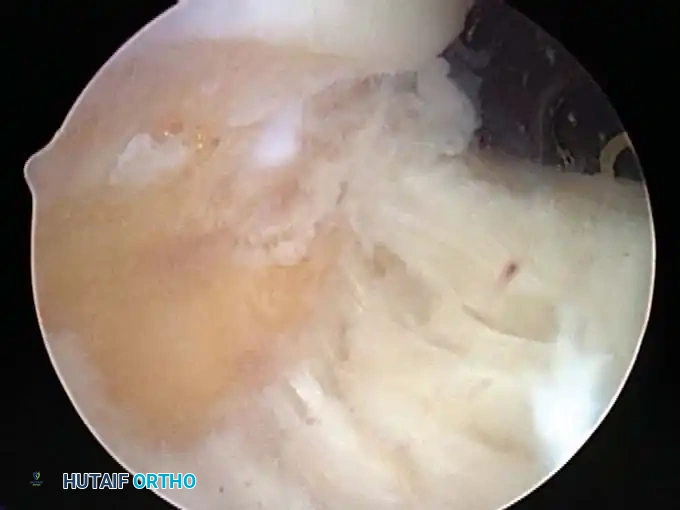

* Calcific Tendinitis: Precise localization and débridement of calcific deposits within the rotator cuff tendons.

Once diagnostic evaluation is complete and hemostasis is secured, the therapeutic phase commences. Whether performing a SLAP repair, a Bankart stabilization, or a rotator cuff repair, the principles of tissue mobilization, anatomical footprint restoration, and secure biomechanical fixation remain paramount.

Modern arthroscopy relies heavily on suture anchors (biocomposite or all-suture constructs) and advanced arthroscopic knot-tying or knotless techniques. The ability to pass sutures through retracted, fibrotic tissue and secure them under appropriate tension without strangulating the microvascular supply is the hallmark of a master arthroscopist.